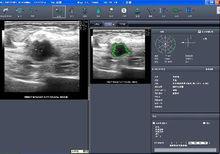

近年來,隨著計算機技術的高速發展,CAD技術在一些醫療已開發國家的相應領域取得了較快的發展,特別是在涉及醫學影像學的領域。實踐證明,CAD在提高診斷準確率、減少漏診、提高工作效率等方面起到了極大的積極促進作用。

CAD研究在20世紀60年代之後一度陷入低谷,究其原因,一方面,由於人們對於CAD期望過高,希望能夠藉助計算機實現自動診斷(automated diagnosis) ;另一方面CAD的研究發展仍然受限於相應的理論算法和原理分析的匱乏。這種內外皆有的雙重困境直到八九十年代,由於計算機技術及各種數學、統計學的快速發展,才得以有了質的改善,在一些已開發國家的醫學影像學領域才獲得較快發展,並取得了可喜的成就。目前,國外學者對於計算機輔助診斷在醫學影像學中的含義基本達成共識,即:套用計算機輔助診斷系統時最終診斷結果仍是由醫生決定的(並不是完全的由機器進行自動診斷),只是醫生在判斷時會參考計算機的輸出結果,這樣使得診斷結果更客觀更準確。目前國外學者強調計算機的輸出結果只是作為一種參考(second opinion),這與最初六七十年代的計算機自動診斷的觀念以及現在某些人對於CAD的理解是不同的。醫學影像學中,計算機的輸出結果是定量分析相關影像資料特點而獲得的,其作用是幫助放射科醫師提高診斷準確性以及對於圖像、疾病解釋的一致性(consistency),另言之,計算機的輸出結果只可以作為一種輔助手段,而不能完全由其進行相應的診斷。CAD之所以能夠提高醫生的診斷準確性,原因在於,在傳統診斷方法中,放射科醫生的診斷完全是主觀判斷過程因而會受到診斷醫生經驗及知識水平的限制和影響;其次,醫生診斷時易於遺漏某些細微改變;再次,不同醫師間及同一醫師間的閱片差異的影響。而計算機客觀的判斷對於糾正這些錯誤和不足具有巨大的優勢 。

計算機輔助診斷的研究套用

計算機輔助診斷目前,CAD研究大多局限在乳腺和胸部肺節節性病變,在CT虛擬結腸內鏡(CTC)、肝臟疾病CT診斷、腦腫瘤MRI診斷等的CAD研究仍很少,而且較不成熟。因而,乳腺及肺結節病變的CAD研究基本上可以代表目前CAD在醫學影像學中的最高水平和現狀 。